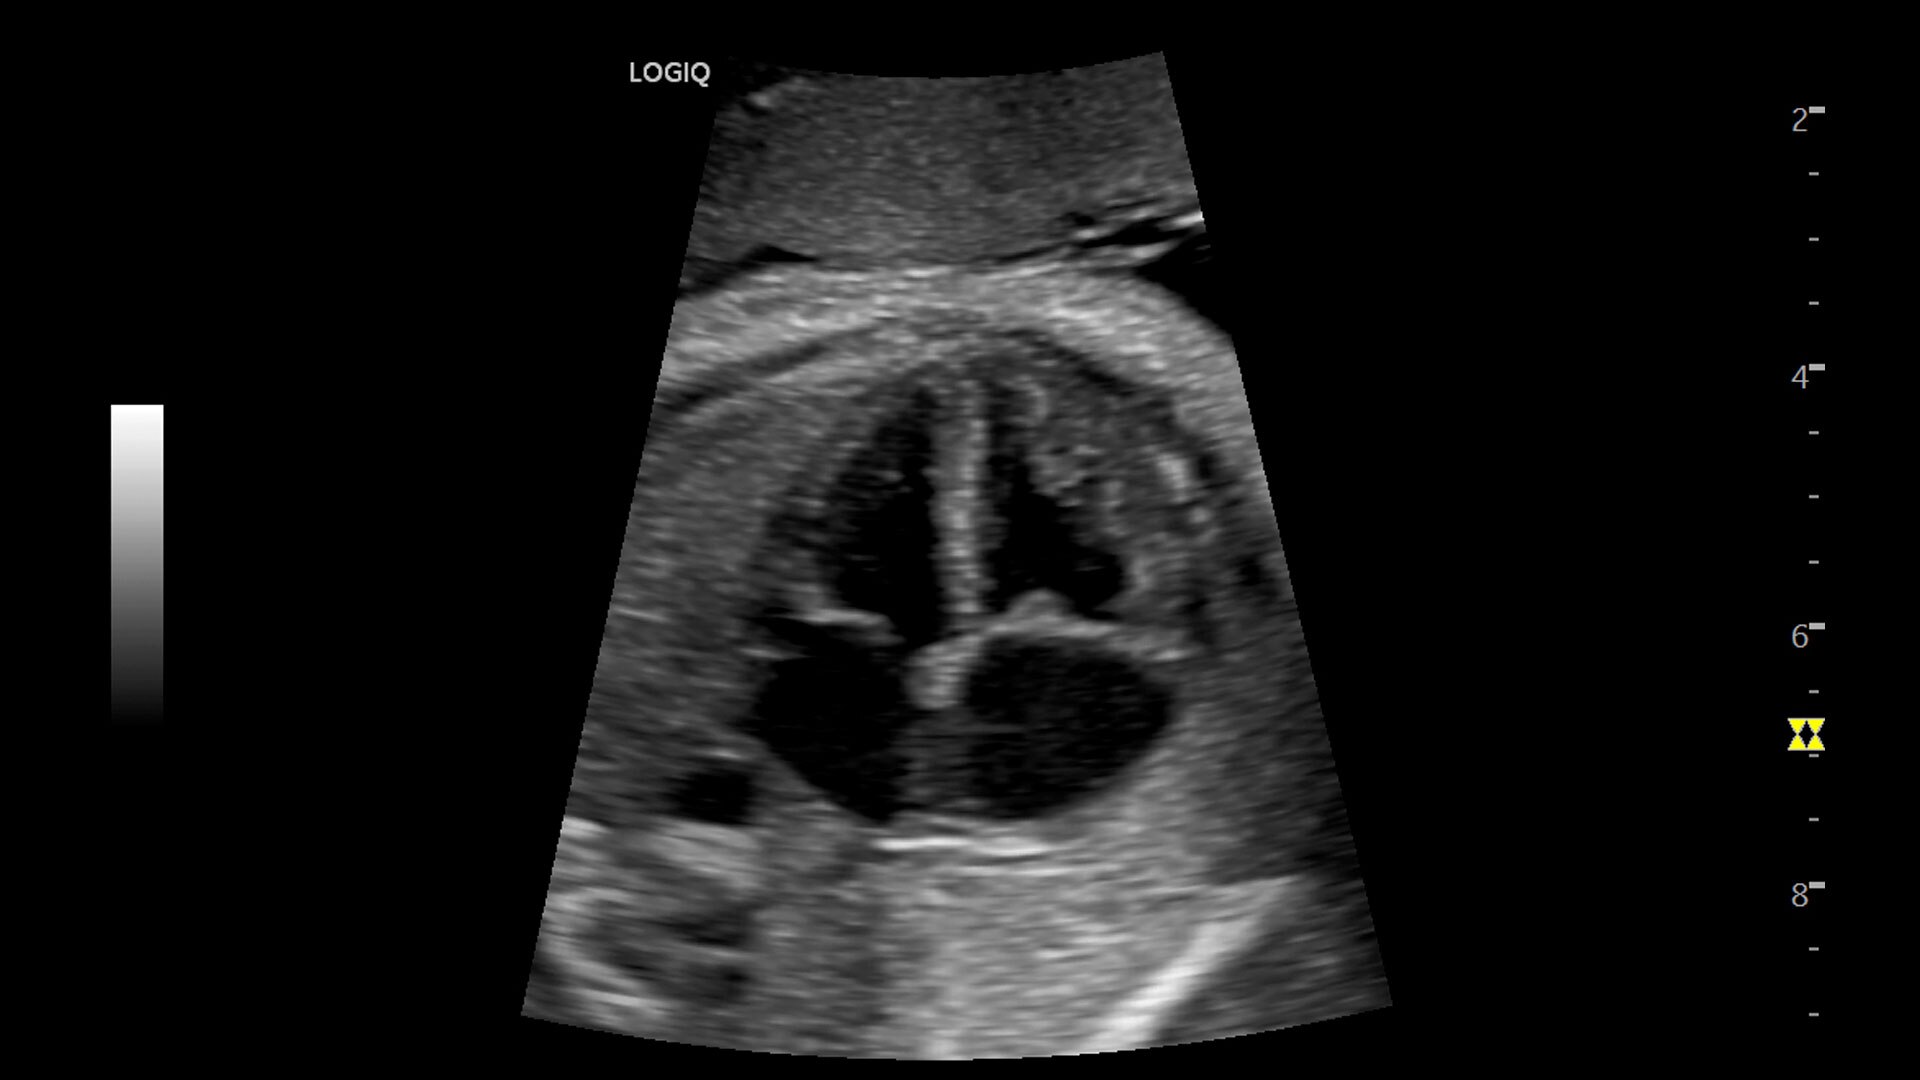

Multi-purpose capabilities, including liver, cardiac, OB/GYN, vascular, breast, thyroid, musculoskeletal, urologic, and pediatric studies.

• 3D/4D with SonoRenderlive